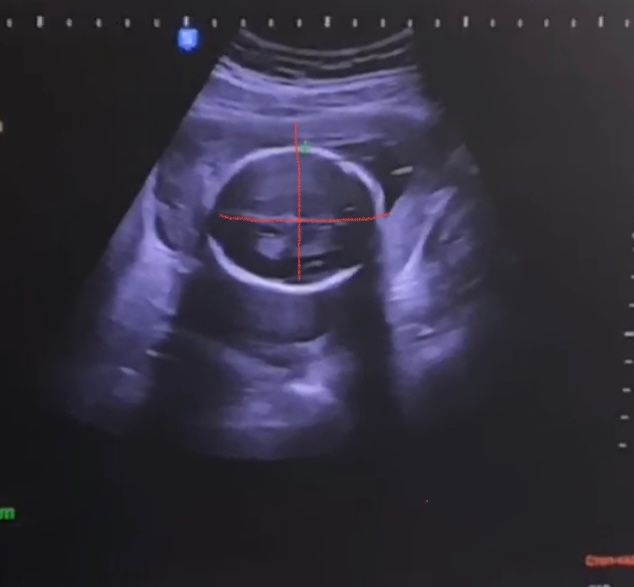

Всем привет! Вчера была на втором скрининге, узист сказала все хорошо, но придя домой обнаружила опечатку в БПР 68!

На видео наглядно видно что голова правильная, лзр 62 и это значение визуально больше бтр

стоит ли переживать по данному поводу?